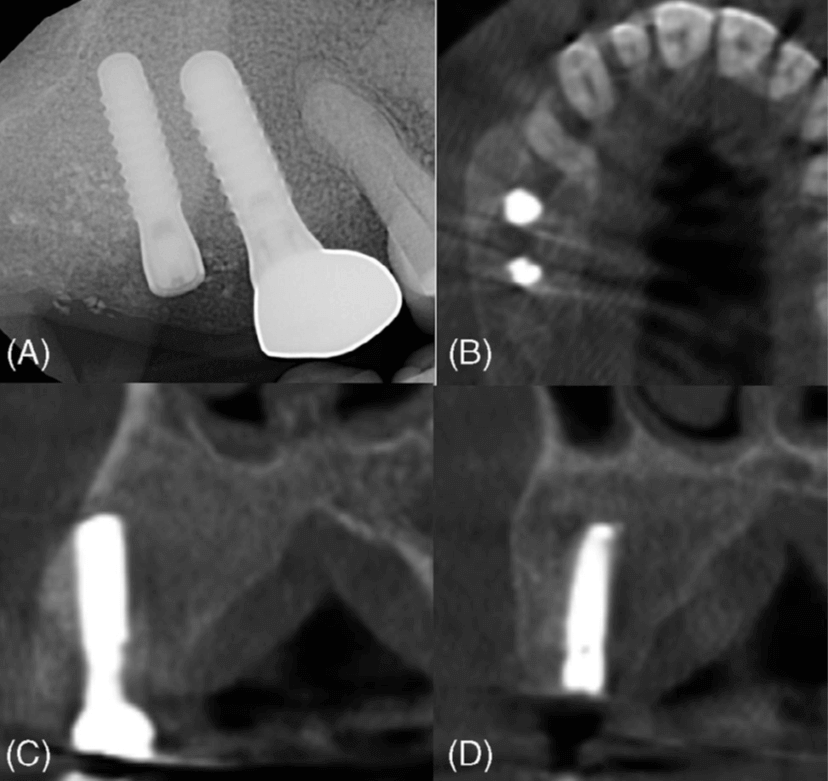

La alteración del contorno del hueso alveolar, la reabsorción o dislocación dental, las relaciones interarcadas anormales y la remodelación de la estructura ósea displásica con el tiempo plantean retos importantes para la rehabilitación oral. Las pruebas sugieren que los implantes dentales pueden tener una alta tasa de supervivencia en pacientes con DF. Una revisión sistemática realizada por Pérez et al. informó de una tasa de supervivencia del 100 % para 36 implantes durante un período de seguimiento medio de 51 meses (4,25 años). Además, un estudio de caso realizado por Monje et al. documentó el éxito de la colocación de un implante en el maxilar izquierdo de un paciente tras Tratamiento DF. Se extrajeron los premolares y el primer molar del paciente y, diez meses después de la extirpación de la lesión, se colocaron implantes. Un periodo de seguimiento de un año mostró una osteointegración satisfactoria, sin signos de inflamación, pérdida ósea ni movilidad. Además, un estudio de caso realizado por Monje et al. documentó el éxito de la colocación de implantes en el maxilar izquierdo de un paciente tras el tratamiento de la DF. Se extrajeron los premolares y el primer molar del paciente y, diez meses después de la extirpación de la lesión, se colocaron los implantes. Un periodo de seguimiento de un año mostró una osteointegración satisfactoria, sin signos de inflamación, pérdida ósea ni movilidad.

La DF representa un subconjunto de diversas displasias óseas que pueden afectar al hueso alveolar, lo que plantea retos únicos en la cirugía oral y maxilofacial. Esta afección altera el proceso normal de remodelación ósea, lo que provoca cambios significativos en la estructura y la estabilidad del hueso. Por consiguiente, es fundamental comprender cómo las displasias óseas como la DF afectan a la osteointegración y a la supervivencia a largo plazo de los implantes dentales. Evaluar los efectos de estas lesiones en el éxito de los implantes es clave para optimizar los resultados de los pacientes y desarrollar estrategias de tratamiento personalizadas. En este caso, un paciente con DF monoestótica en el lado derecho del maxilar superior fue tratado con éxito remodelando toda la lesión y conservando los implantes dentales. Los implantes no mostraron signos de movilidad clínica ni de recurrencia de la enfermedad.